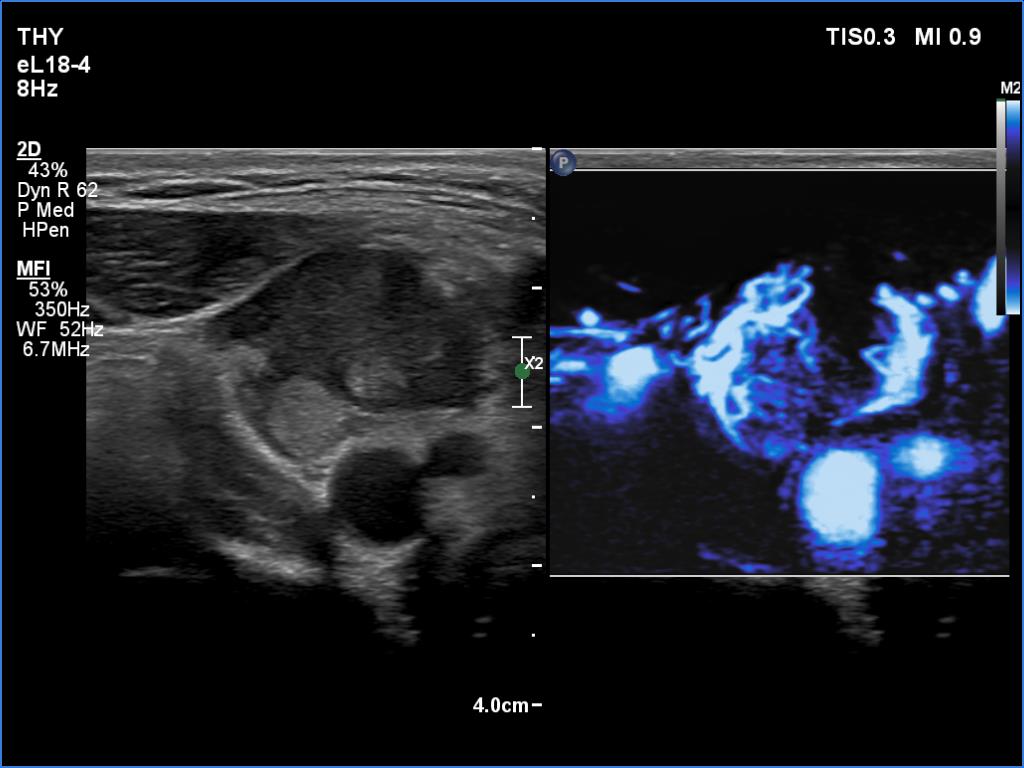

Right submandibular area, transverse scan, microflow imaging. The mass is rich in vessels.